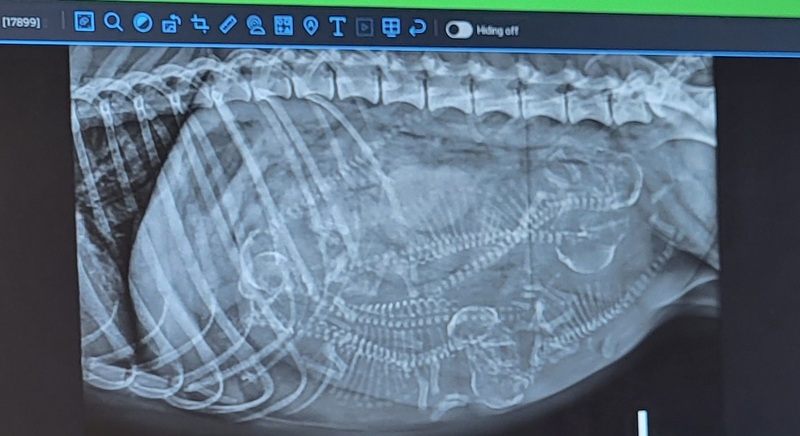

Shih Tzu: AKC preregistered as well as microchipped and preregistered with AKC ReUnite. DNA tested parents in good standing with no transfer of disease. OFA tested and registered parents in good standing all average or better. An extended refund option if it doesn't work out for the entire life of the dog in percentage increments according to the dog's age. 30 days free insurance. Vaccinated with DHPP. Exam by a veterinarian. A go home bag with a toy, chew, Purina Pro Plan all life stages kibble, a leash and collar/harness, book. Potty trained to outside concrete and pine pellet litter box as well as the Brilliant Pad. I also work on confined crate training and car rides. Grooming, bathes, nails, feet and fanny trimming. Often an in-utero x-ray or ultrasound. The go home bag and registrations and vet care add up to a $750 value that most don't provide. That doesn't account for the cost of operation adding up to $4000 per dog every year on average without accounting for my time or facility improvements. Because I follow the guidelines of ethical breeding practices, I only have a small handful of pups per year and my costs are greater with all the upfront OFA certifications and health testing. Please do not purchase until we have talked and discussed pick up or optional transportation as fees are separate and in addition to the puppy price and dependent on distance. A general rule is the ticket price from ROA / RNK x2 plus a hotel if needed. Sometimes I have retired shih tzu for a smaller price tag if you would prefer. Please contact me at boss@mountainpassbarn.com for a pick up address. What you get when you purchase a pup from me: - Preregistration with the AKC a $40 value - AKC ReUnite microchipped and preregistered a $40 value - Pups get baths and nails at a $40 value each time - Kindergarten pups get outside and/or pine pellet box potty training started according to weather - Obstacles, balance boards, puzzles, and more make confident pups - priceless $ - Confined crate training for a few hours at a time begin crate potty training - car rides and fieldtrips - DNA tested parents in over 200 genetic markers by Embark a $240 value - OFA tested parents registered with the database at $15 each test submitted - OFA's range from $35 to $500 - Pups get an exam by a veterinarian, a $50 value - Full refund in the first 4 days and/or 2 years with a necropsy and/or a partial refund for the life of the dog according to age as detailed in the contract - seriously priceless $ - Go Home bag, travel box if you are traveling alone with no car carrier, Pro Plan all stages kibble food, toy/chew, leash, breed information, and more at a $70 value - You are permitted to come to the house for pick up. This is an option that most won't allow. Priceless$ CONTACT via EMAIL FOR PICK UP ADDRESS as this is a private residence : boss@mountainpassbarn.com - I provide transportation for a fee - The go home bag and registrations and vet care add up to a $750 value that most don't provide. That doesn't account for the cost of operation adding up to $4000 per dog every year on average without accounting for my time or facility improvements. Because I follow the guidelines of ethical breeding practices, I only have a small handful of pups per year and my costs are greater with all the upfront OFA certifications and health testing. Please do not purchase until we have talked and discussed pick up or optional transportation fees are separate and in addition to the puppy price and dependent on distance. A general rule is the ticket price from ROA / RNK x2 plus a hotel if needed and I have to pay my transporters for time. Delivery by car up to around 100 miles from Roanoke Va is $300 and delivery by train to Alexandria (ALX) or DC (WAS) is $300.